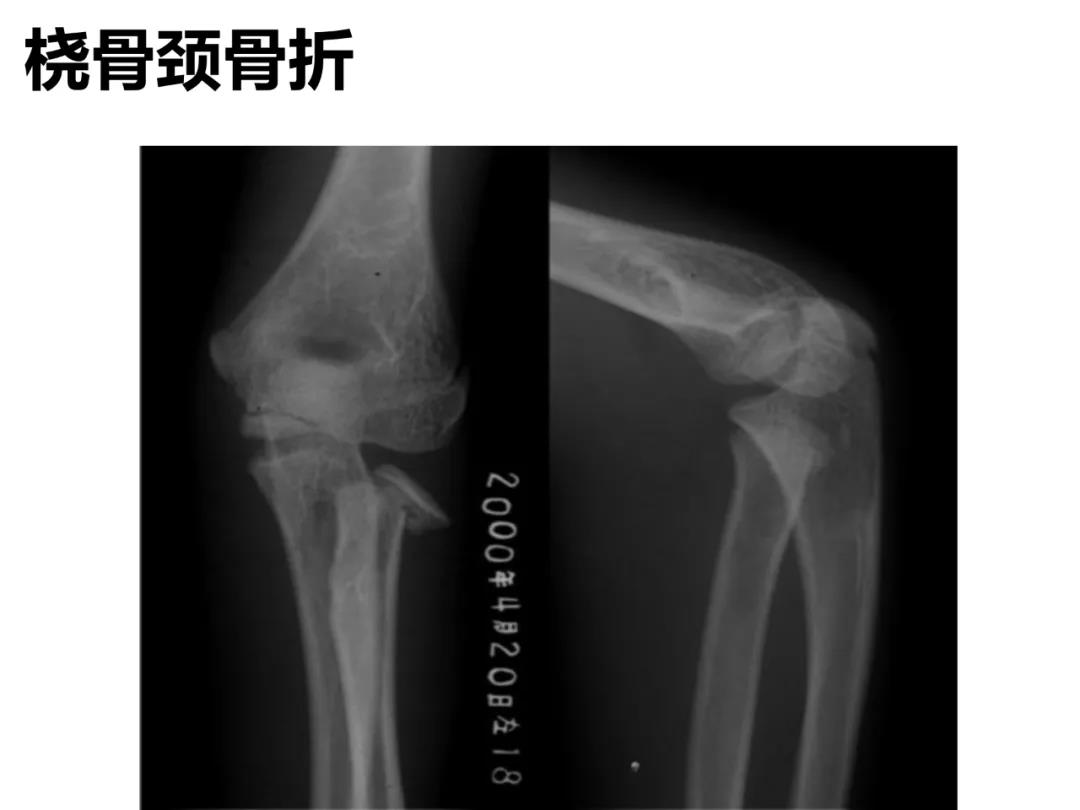

小儿骨科X线片汇总,临床读片宝典!